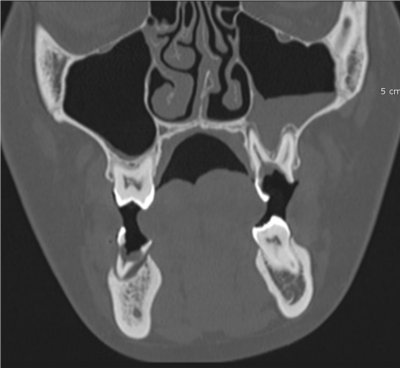

Le cone beam utilisé en pathologie dentaire et maxillo-faciale est indiqué pour l’examen des tissus minéralisés (dents, cartilages, os), il permet d’identifier les lésions osseuses, les fractures, les infections, les kystes ou les corps étrangers.

- pathologie des sinus maxillaires

Les nouvelles générations de scanner permettent de faire une acquisition d’un volume global d’une partie du corps et de travailler à l’intérieur de ce volume en isolant une structure anatomique donnée et de l’explorer dans tous les plans de l’espace.

Grace à la technique de seuillage il est possible de dissocier progressivement les dents des structures osseuses environnantes dans le volume donné.